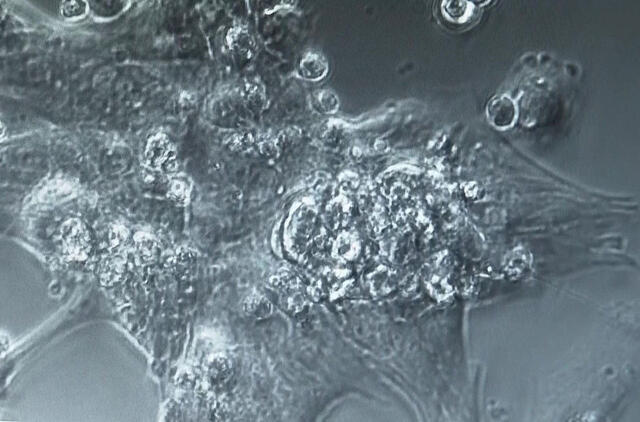

Mokslininkai laboratorijoje augina širdies ląsteles, kad sukurtų dirbtinio intelekto įrankį, galintį greičiau aptikti širdies ląstelių ligas.

Rytų Londono universiteto komanda tiria, kaip senstant suserga širdies ląstelės.

Nauju bandymu tyrėjų komanda bando imituoti širdies kraujo siurbimo funkciją, žiūrėdama į sistolių ir diastolinių susitraukimų seriją ir išmatuodama jų greitį bei modelį.